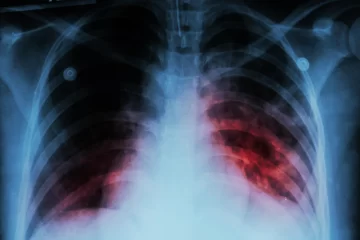

Se trata de una enfermedad infecciosa que afecta a los pulmones y que es causada por una bacteria (Mycobacterium tuberculosis) que se transmite de una persona a otra a través de las gotitas de aerosol que permanecen en el aire tras haber sido expulsadas por personas con enfermedad pulmonar activa. Se estima que una cuarta parte de la población mundial está infectada por el bacilo de la tuberculosis, pero (aún) no ha enfermado ni pueden transmitir la infección. Este grupo de personas infectadas de forma latente tiene un riesgo de enfermar de tuberculosis a lo largo de su vida de entre el 5% y el 10%.

Los principales síntomas de esta enfermedad son: tos (a veces con esputo que puede ser sanguinolento), dolor torácico, debilidad, pérdida de peso, fiebre y sudoración nocturna. Es importante considerar que los síntomas dependen de la magnitud del compromiso, del tiempo de evolución del cuadro, de la edad y del estado inmunológico del paciente. Estos signos, a veces solapados durante muchos meses, ocasionan retrasos en la búsqueda de la atención médica y en la detección. Muchas veces, el cuadro se puede confundir con otras enfermedades y cuanto mayor es la demora en el diagnóstico de la enfermedad, hay un mayor riesgo de contagio a otras personas.